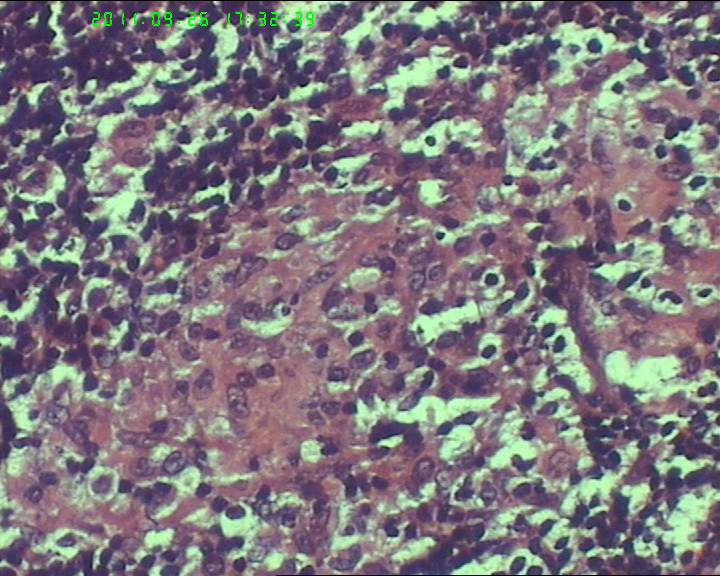

21岁女性左侧颌下淋巴结,该诊断什么?

灰白不整形肿物一个,大小3.5*2.5*2cm,包膜完整。

21岁女性左侧颌下淋巴结,该诊断什么?图4

慢性肉芽肿性炎症,形态学倾向结节病,但是作为病理工作者对于这样的病例,再结合咋们国情,还是建议临床除外增殖性结核后再考虑结节病。

肉芽肿性炎症,倾向结节病。

肉芽肿性炎,考虑结核不除外结节病